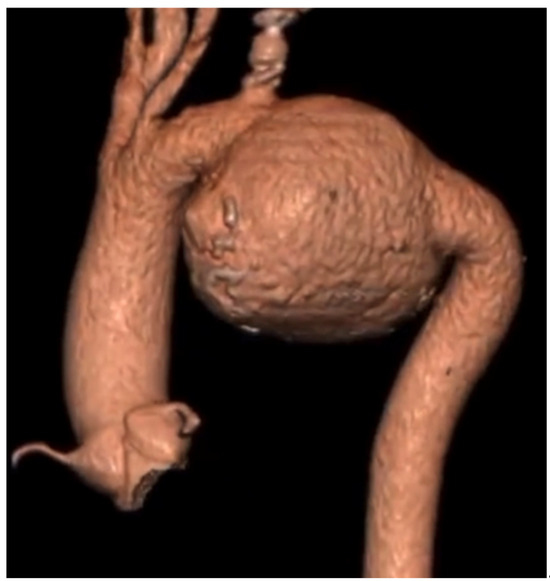

| Current Case-1 | 48 | M | Aortic arch | Cough | 25 years | Hybrid (ET + TEVAR) |

| Current Case-2 | 46 | M | Aortic arch | Asymptomatic | 21 years | Hybrid (carotid-subclavian bypass + TEVAR) |